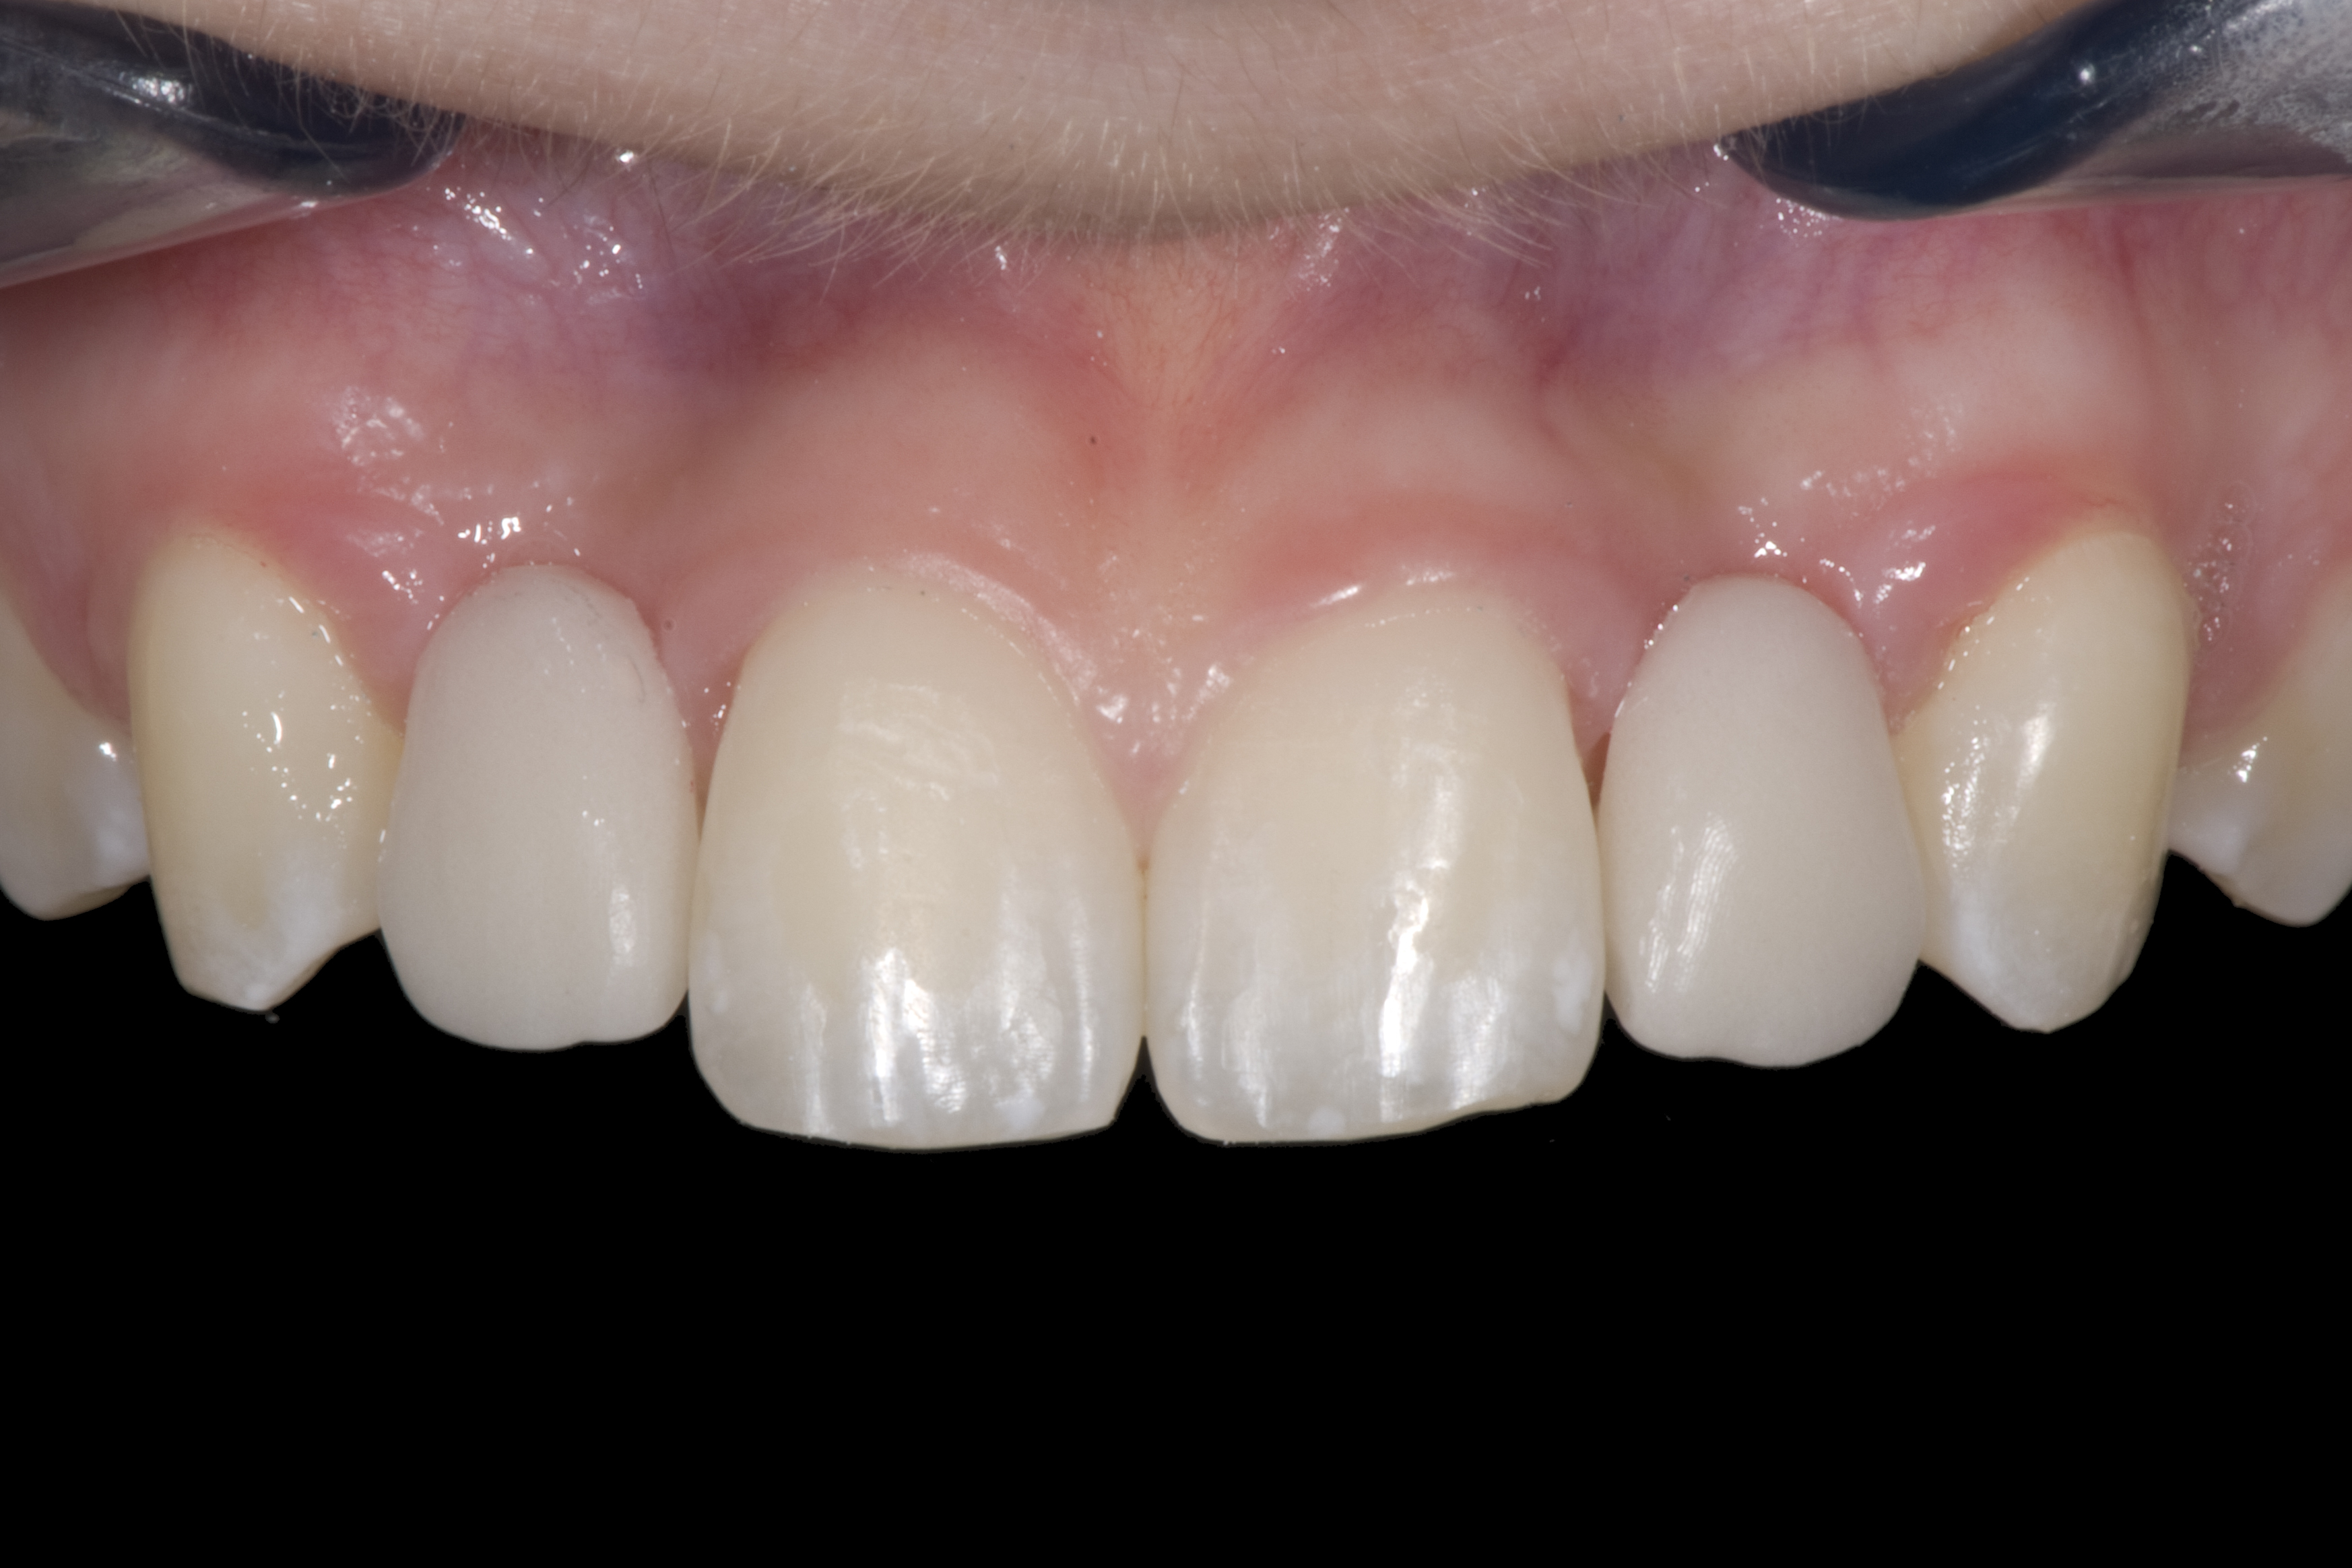

(20.) Facial view of final single-wing, modified zirconia resin-bonded bridges.

Figure 20

When the patient returned, the fit was evaluated in the mouth. Once verified, the internal surface of the framework was etched with a 9.5% hydrofluoric acid for 90 seconds and then salinized. After etching the enamel surface with phosphoric acid for 30 seconds and applying the primer (Single Bond Plus, 3M ESPE) to both the internal surface of the framework and the enamel, the zirconia bridge was bonded with a dual-cure resin cement (RelyX™ ARC, 3M ESPE). After the procedure, the patient ended up with a long-term, high-strength esthetic restoration advantaged by the bonding potential of fledspathic ceramic (Figure 20 through Figure 24). Six years after placement, the prosthesis had remained in place with no complications.